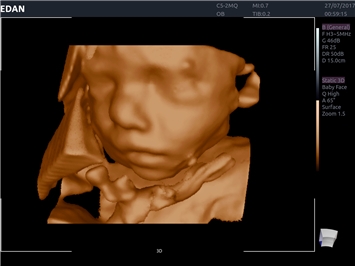

• 3D/4D-визуализация с автоматическим редактированием объема (eFace)